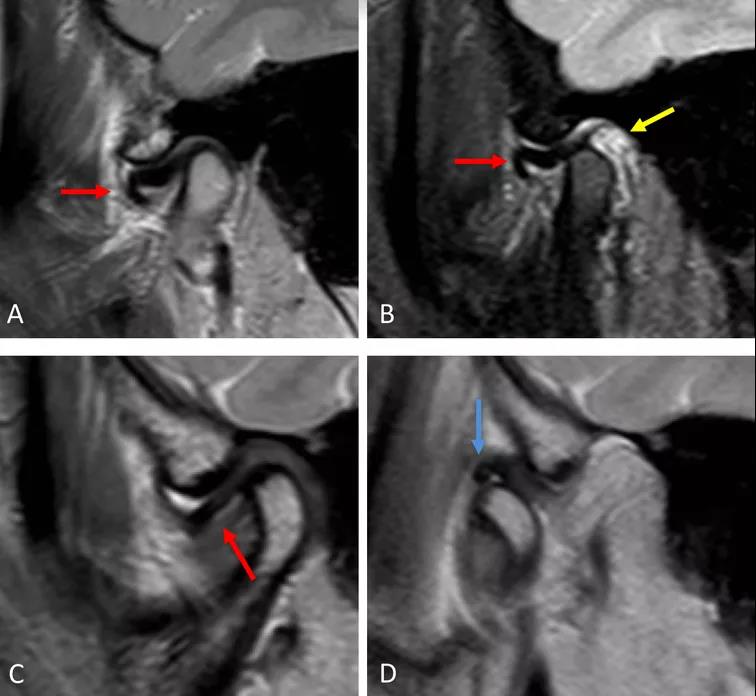

病例一:斜矢狀平面上的質(zhì)子密度加權(quán)圖像(PDWI)

A圖示:閉口位時(shí),顯示關(guān)節(jié)盤前移位明顯,雙凹形態(tài)消失。注意前帶的下移位(紅色箭頭)。

B圖示:張口位時(shí),顯示關(guān)節(jié)盤移位(紅色箭頭),關(guān)節(jié)積液(黃色箭頭)。病例2:斜矢狀平面上的質(zhì)子密度加權(quán)圖像(PDWI)